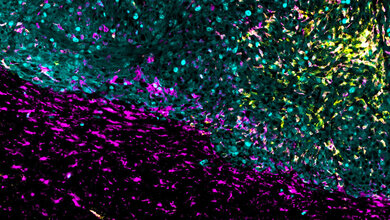

In der Krebsmedizin wird zudem für viele Menschen die Translation neuer Erkenntnisse in die Versorgung direkt sichtbar. So sind für einige Krebserkrankungen Immuntherapeutika in Deutschland bereits in der Routine angekommen.